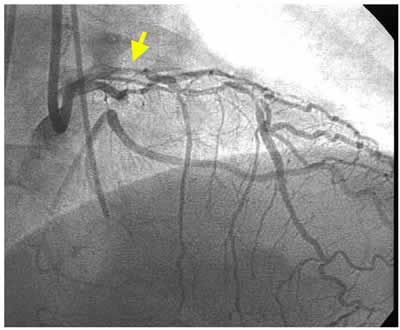

J-4 : 3 months follow-up angio